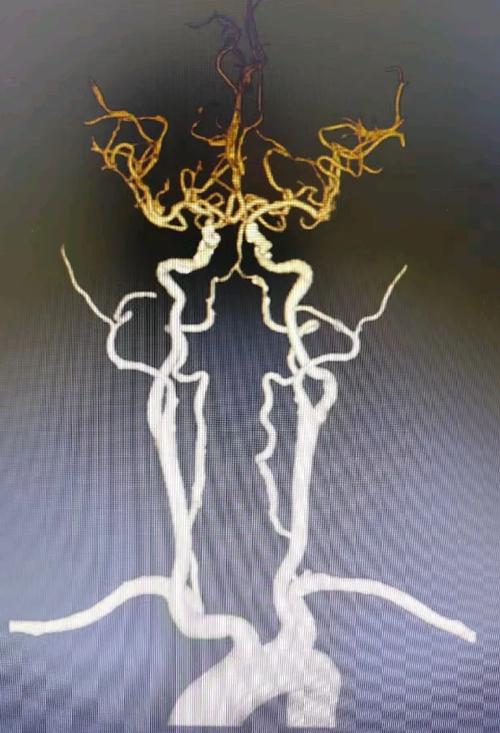

解密心脏CTA:看清“心脑动脉”的“路况”

心脏CTA(Computed Tomography Angiography),全称“冠状动脉CT血管成像”, 是一种无创、高效的检查方法,它通过静脉注射造影剂,利用多层螺旋CT对心脏冠状动脉及其主要分支进行三维成像,能够清晰显示血管的狭窄、斑块、畸形等情况。

- 评估冠心病严重程度: 冠心病患者往往同时存在全身动脉粥样硬化,包括颈动脉、椎动脉等脑供血动脉,严重的冠心病意味着患者发生心脑血管事件(包括脑梗)的风险显著增高,心脏CTA能明确冠心病的病变范围和严重程度,为风险评估提供关键依据。